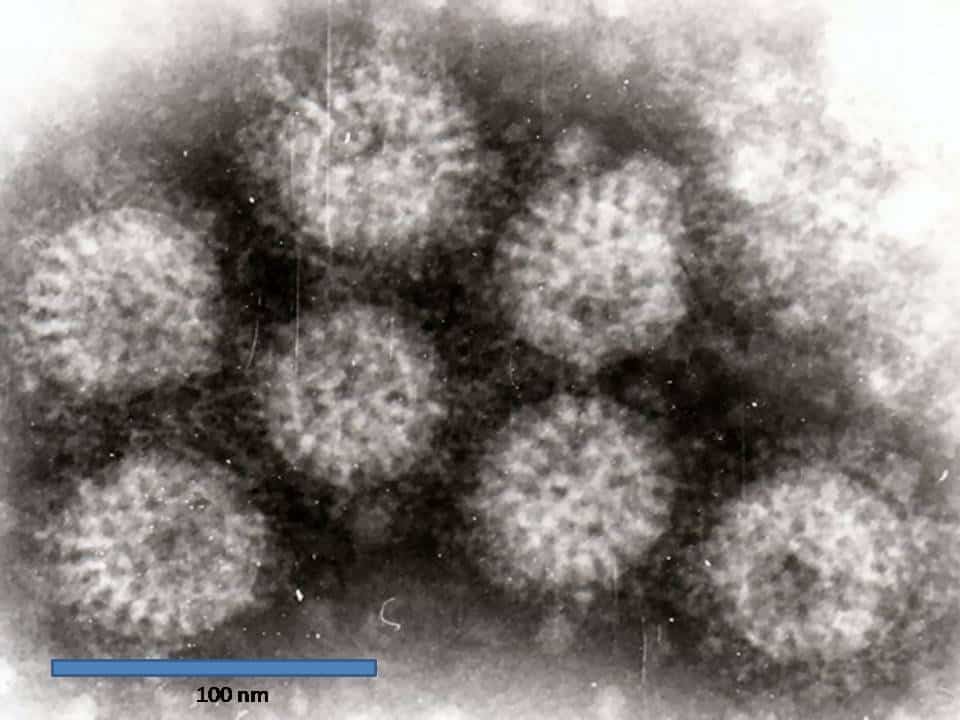

- Norovirus – single-stranded RNA virus (Fig. 1), the most common form of viral gastroenteritis in adults, presents with abdominal cramps, watery diarrhoea, and vomiting, usually lasting 1-3 days

Figure 1 – Rotavirus particles, as seen on electron microscopy